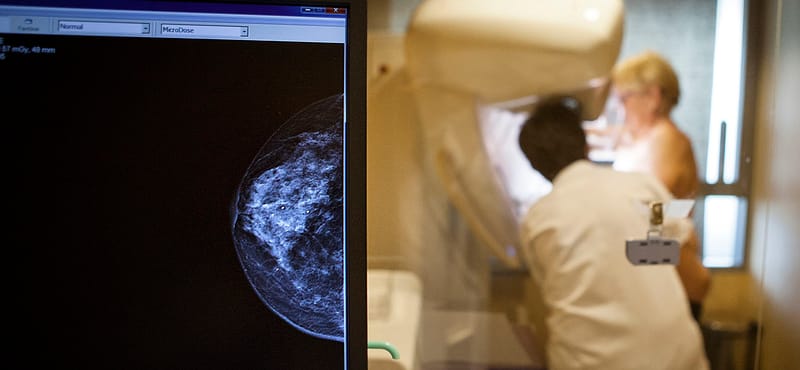

Miért van az, hogy a 3D-s képeken több infó van, mégis kevesebbet látunk belőle?

Hiába ígér óriási előnyöket egy új technológia, ha az emberi képességek akadályt állíthatnak az útjába – foglalható össze amerikai kutatók megfigyelése. Bár a háromdimenziós képek sokkal több információt tartalmaznak, mint a síkbeliek, bizonyos esetekben az emberi szem jobban eligazodik ez utóbbiakon – írják a Kaliforniai Egyetem szakemberei tanulmányukban.